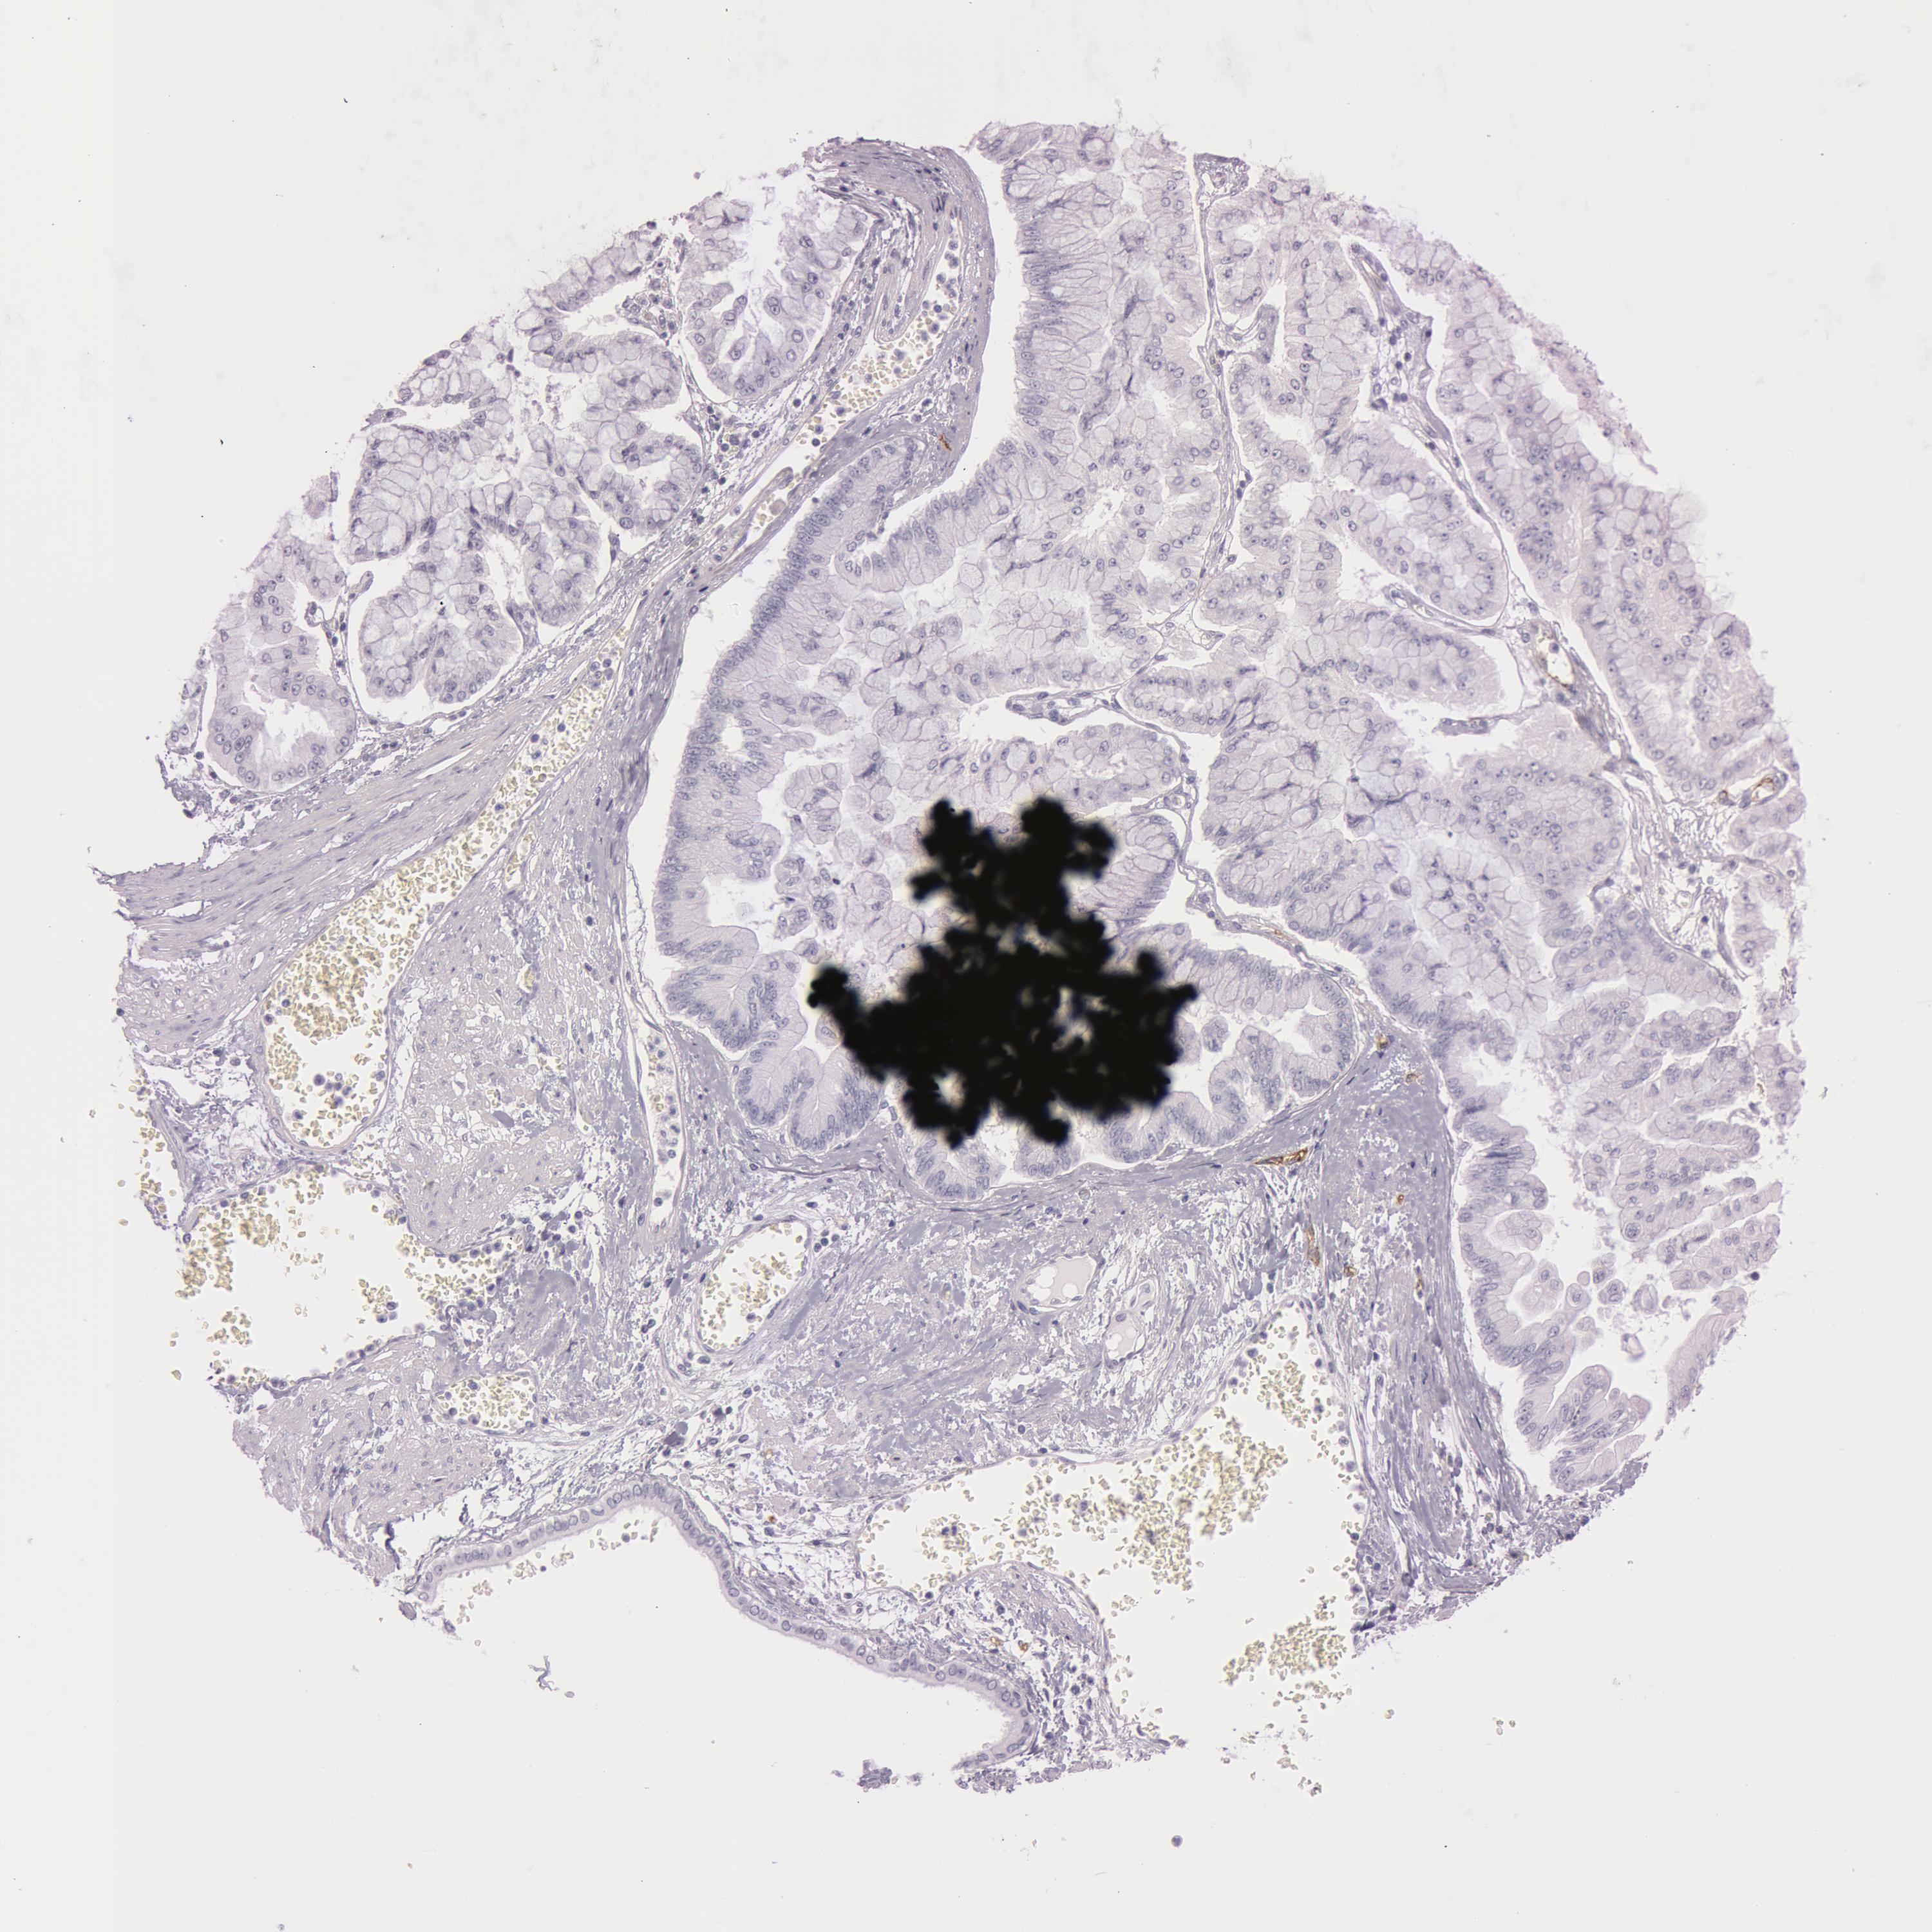

LIVER CANCER - Protein expressioni

A mouse-over function shows sample information and annotation data. Click on an image to view it in a full screen mode. Samples can be filtered based on level of antibody staining by selecting one or several of the following categories: high, medium, low and not detected. The assay and annotation is described here.

Note that samples used for immunohistochemistry by the Human Protein Atlas do not correspond to samples in the TCGA dataset.

Antibody stainingi

Antibody staining in the annotated cell types in the current human tissue is reported as not detected, low, medium, or high, based on conventional immunohistochemistry profiling in selected tissues. This score is based on the combination of the staining intensity and fraction of stained cells.

Each image is clickable and will lead to virtual microscopy that enables deeper exploration of all samples and also displays staining intensity scores, fraction scores and subcellular localization as well as patient and tissue information for each sample.

Antibody HPA010593

Antibody CAB001451

Staining

High

Medium

Low

Not detected

Intensity

Strong

Moderate

Weak

Negative

Quantity

>75%

75%-25%

<25%

None

Location

Nuclear

Cytoplasmic/membranous

Cytoplasmic/membranous,nuclear

Cholangiocarcinoma

Carcinoma, Hepatocellular, NOS